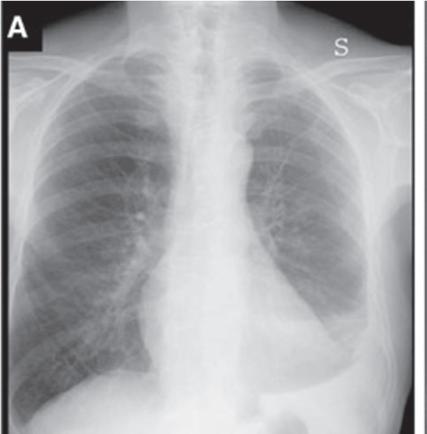

In digital tomosynthesis, multiple projections (about 60) of very low-dose x-rays are obtained through the region of interest during a breath-hold of 10 seconds. The acquired data are then reconstructed into contiguous coronal images. At total estimated effective dose of about 0.12 mSv, the radiation dose from digital tomosynthesis is higher than typical PA chest radiographs (0.02 mSv) but significantly lower than most chest CT examinations (2–6 mSv). Compared with plain radiography, digital tomosynthesis provides superior lesion detectability from noise reduction, better depth assessment, and superior contrast resolution. Although the driving application of chest digital tomosynthesis is improved detection of pulmonary nodules over conventional radiography, several other applications have been assessed as well—for example, suspected interstitial lung disease, cystic fibrosis, airway evaluation, and evaluation of thoracic skeleton fractures. Studies have shown that digital tomosynthesis can help detect more pulmonary nodules smaller than 9 mm in diameter compared with combined PA and lateral chest radiographs (Fig. 1.8).

FIGURE 1.8 Digital tomosynthesis. A nodule in the left mid-lung zone on a standard radiograph (arrow) (A) is better seen on a radiograph obtained with the digital tomosynthesis technique (B). Chest computed tomography demonstrates the lung nodule in the left upper lobe (C). (From Terzi A, Bertolaccini L, Viti A, et al: Lung cancer detection with digital chest tomosynthesis: baseline results from the observational study SOS. J Thorac Oncol 2013;8(6):685-692.)